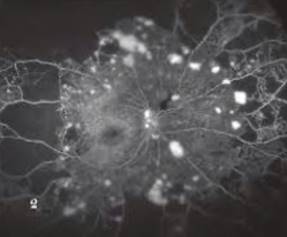

Hình ảnh chụp huỳnh quang võng mạc

Tổn thương đáy mắt do bệnh đái tháo đường